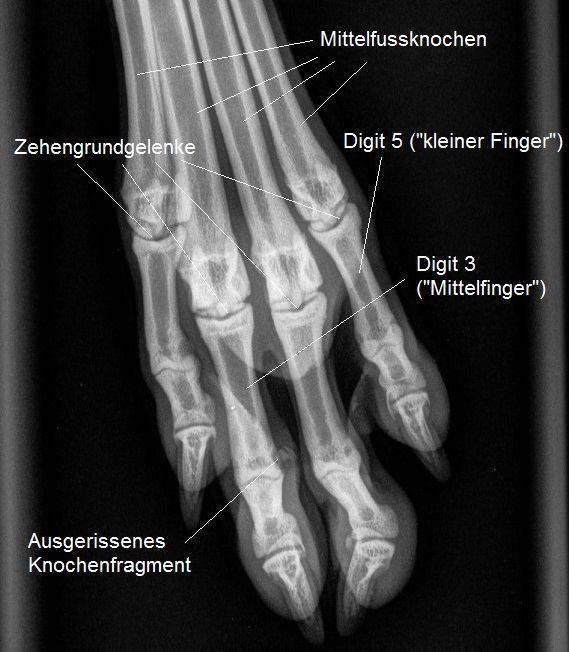

Die Pfote wird geröntgt - hier ist ersichtlich, dass es sich beim ertasteten Knötchen um ein Knochenfragment handelt, welches ganz offensichtlich mitsamt dem Zehen-Seitenband aus dem Zehenknochen ausgerissen worden ist.

Vorsichtig werden Pfote und Hinterbein abgetastet, was bei dieser zappeligen Hündin nicht ganz einfach ist. Das Knie erscheint schmerzfrei und stabil, ein Kreuzbandriss deshalb sehr unwahrscheinlich. Hingegen ist auf der Aussenseite des proximalen Interphalangealgelenks ("Fingermittelgelenk") der 3. Zehe ("Mittelfinger") ein stecknadelkopfgrosses Knötchen unter der Haut zu spüren. Die Einwärtsbiegung des Gelenkes ist sehr deutlich schmerzhaft, ausserdem ist die Biegung sehr viel stärker möglich als beim entsprechenden Gelenk der rechten Hinterpfote. Insbesondere der zweite Befund ist sehr verdächtig für ein Riss des äusseren Seitenbandes dieses Gelenkes.